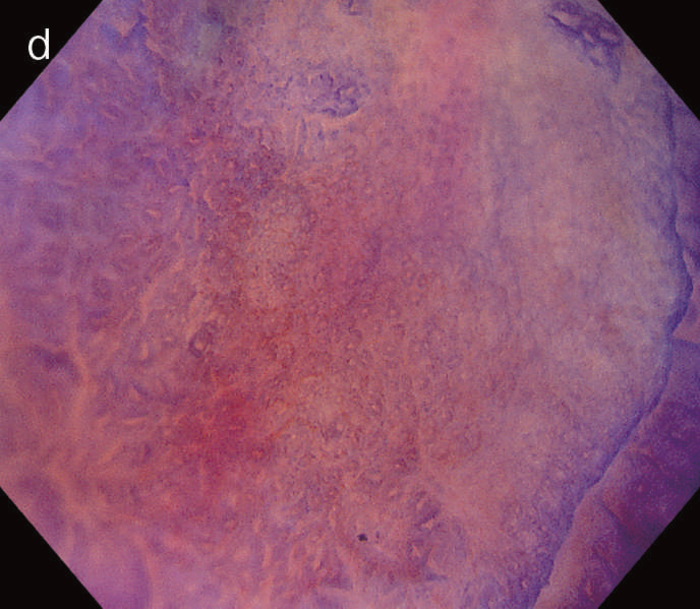

- 白色光像:直腸(直腸S状部)の発赤調変化。背景粘膜は寛解期にあった。

- 色素内視鏡像:病変辺縁が明瞭となるが,病変肛門側で不明瞭であった。

- NBI拡大像:口径不同,不均一な微小血管と不整な表面構造所見を認めた。

- pit pattern像:小型の類円形,管状pitを認めた。